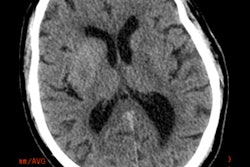

In the 3D volume rendering above, the reader can see a patient-specific color map, indicating the arrival time of blood to the brain. The color difference between the left and right hemisphere is caused by a vascular occlusion in the M1 segment. Due to collateral flow, the affected hemisphere is supplied with blood at a later arrival time, with orange and red hues indicating contrast arrival times several seconds later than green and blue. The green image below lacks color coding and took longer to interpret. Images courtesy of Midas Meijs.Overall, the average time to detection decreased from 37 seconds to 19.4 seconds (p < 0.03), and the average accuracy of vessel occlusion detection increased insignificantly from 0.825 to 0.85 with the use of color mapping. A single false-positive vessel occlusion was called by both observers using color mapping. However, both observers found the technique helpful and time-saving.